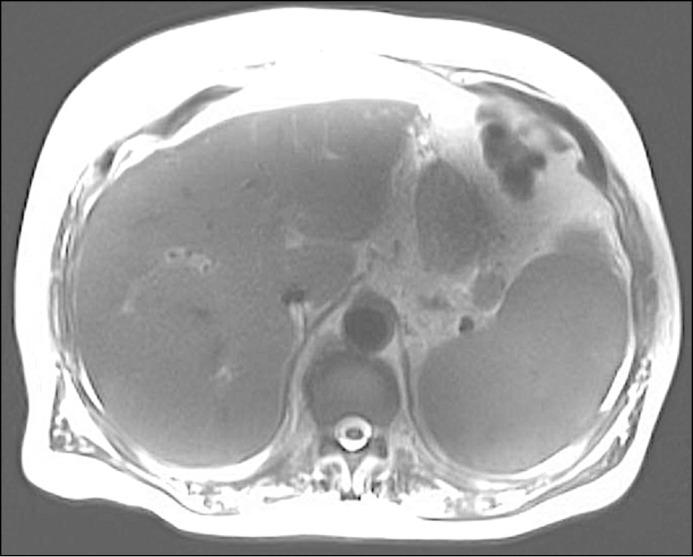

Liver failure is rarely caused by multiple myeloma (MM). We present an unusual case of MM initially presenting as acute liver injury. A 79-year-old man with new-onset fatigue, decreased appetite, and no history of liver disease was found to have evidence of hepatic decompensation. Liver biopsy demonstrated diffuse plasma cell infiltration, and MM was confirmed with bone marrow biopsy. Chemotherapy was initiated, but the patient decompensated and died due to respiratory failure. MM should be considered on the differential for acute decompensated liver disease. Hepatic involvement of MM at presentation is a poor prognostic indicator, and prompt initiation of treatment can be life-saving.

肝功能衰竭很少由多发性骨髓瘤(MM)引起。我们报告了一例不寻常的MM病例,最初表现为急性肝损伤。一名79岁男性,新发疲劳、食欲减退,无肝脏疾病史,被发现有肝失代偿的证据。肝活检显示弥漫性浆细胞浸润,骨髓活检确诊为MM。开始化疗,但患者因呼吸衰竭病情恶化并死亡。对于急性失代偿性肝病的鉴别诊断应考虑MM。MM在发病时累及肝脏是一个不良预后指标,及时开始治疗可挽救生命。